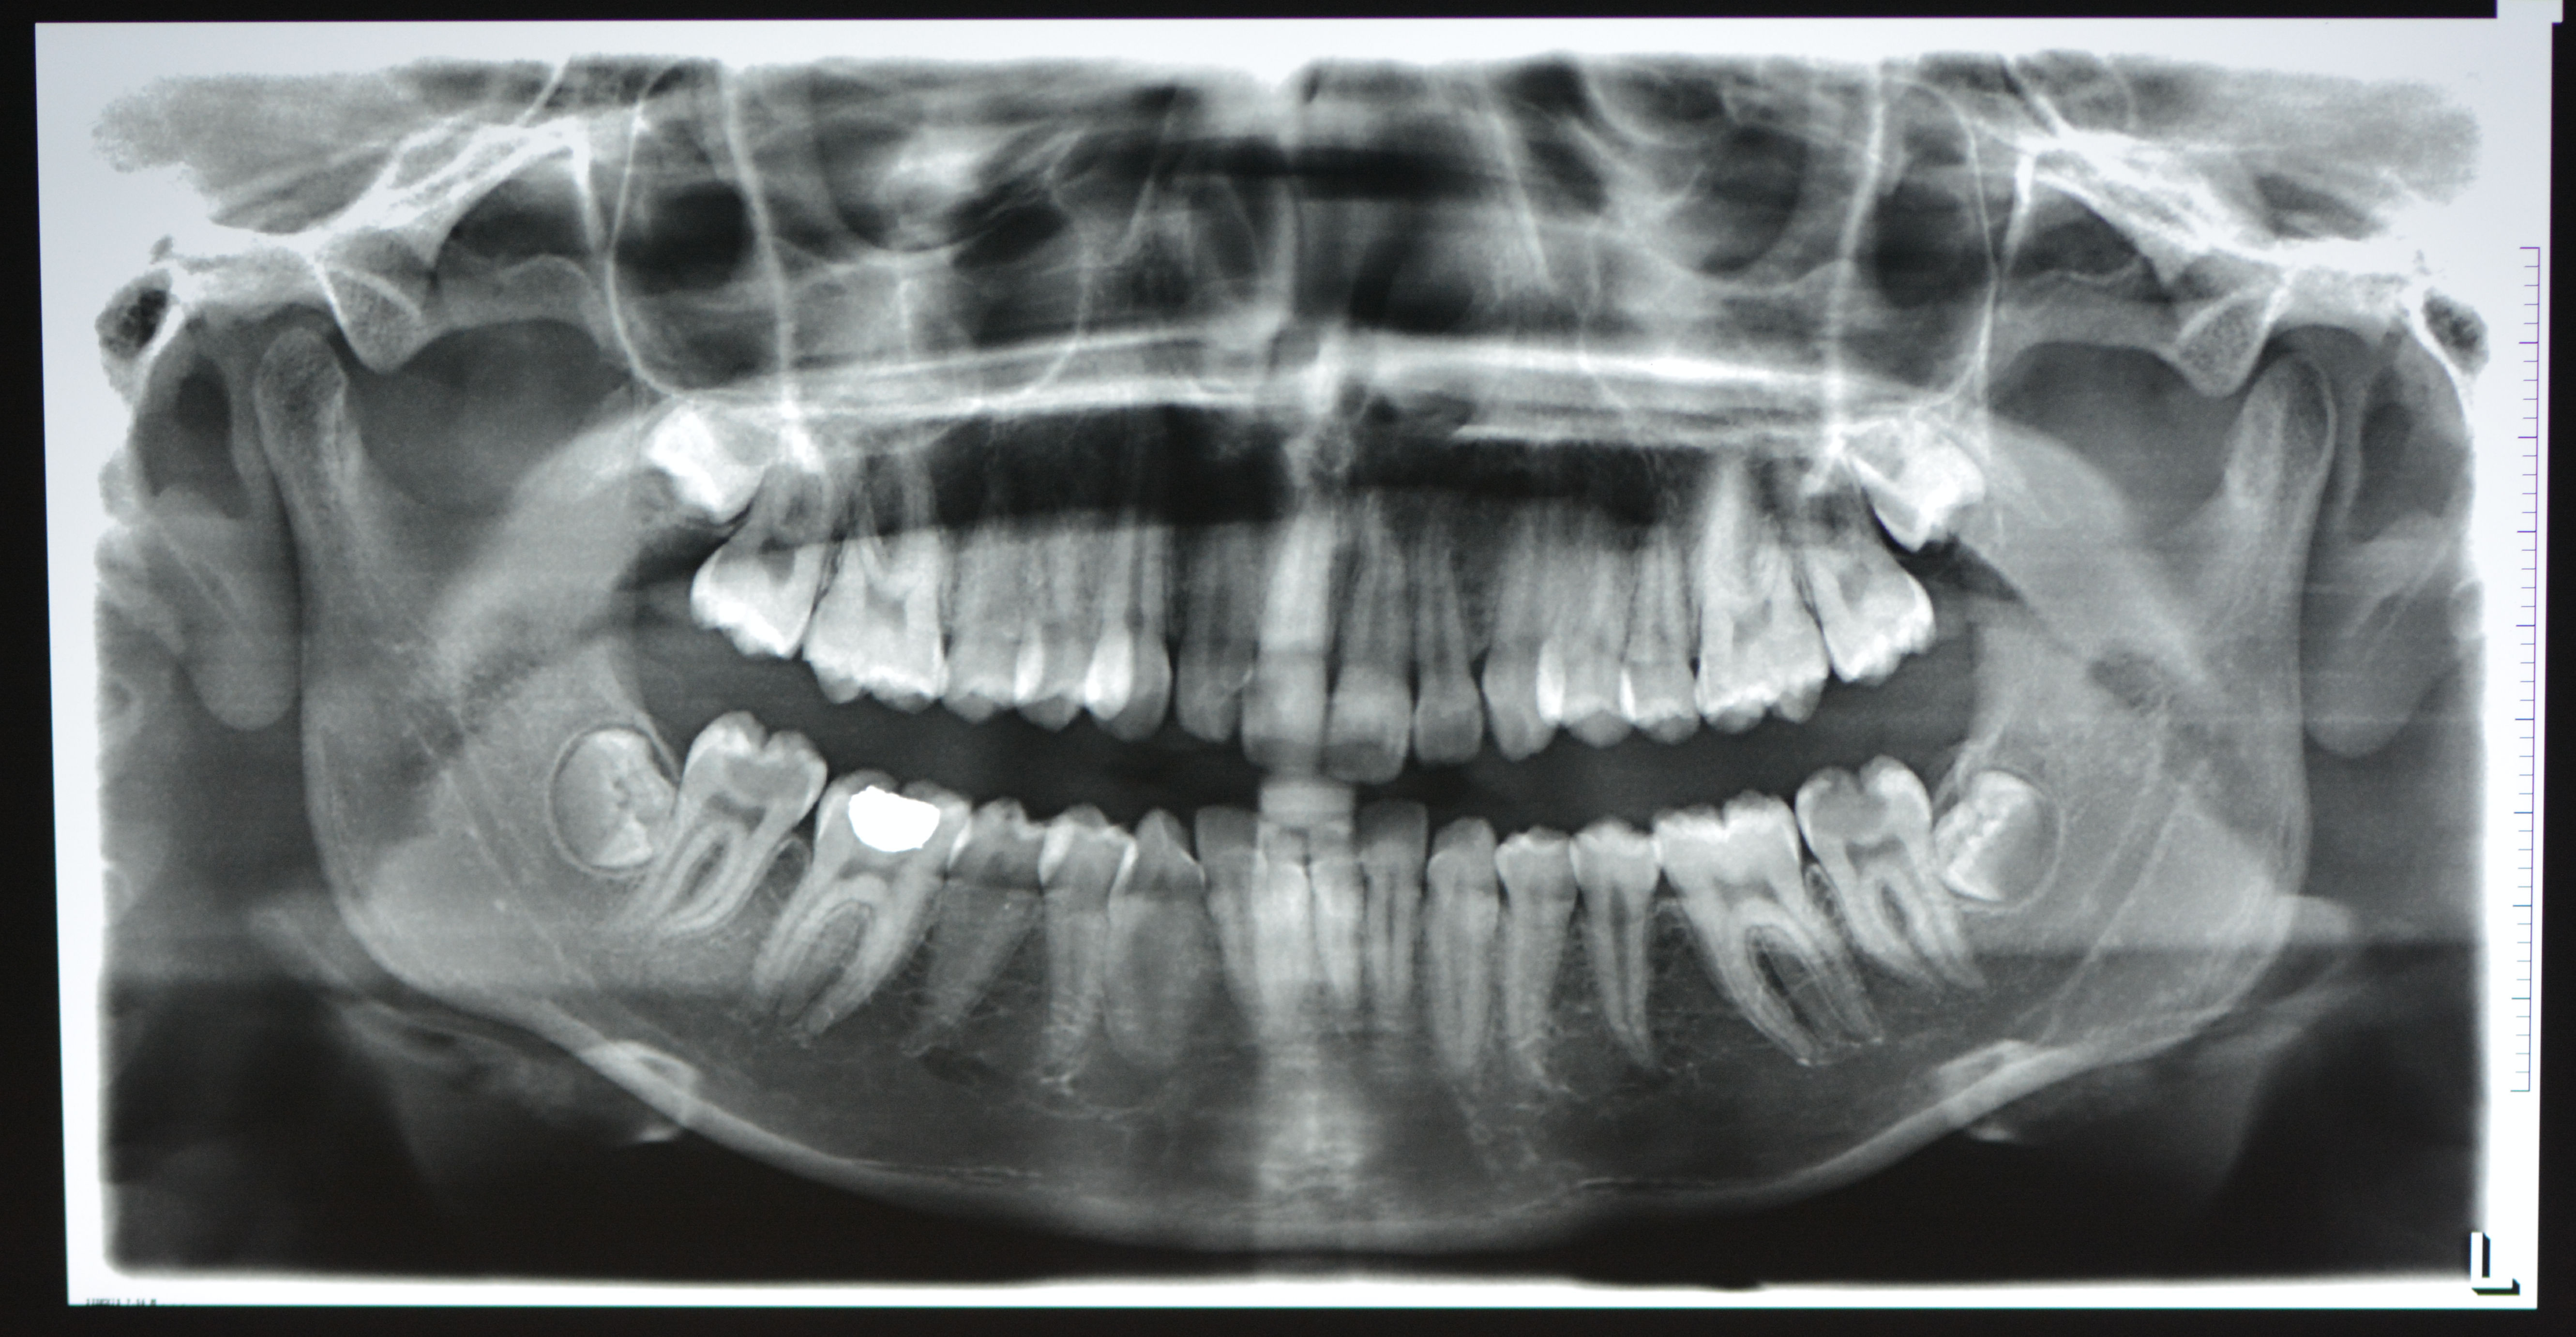

Methods: A 16 year old girl presented with bilateral carious mandibular second molars. She had symptoms of irreversible pulpitis in both the teeth. Parents refused extractuions and were reluctant to proceed with root canal therapy. After informed consent Biodentine Pulpotomy was attempted on both teeth followed by permanent composite resin restorations.

Results: The patient became asymptomatic in both teeth after the procedure. Vital radicular pulp was preserved and root canal treatment avoided